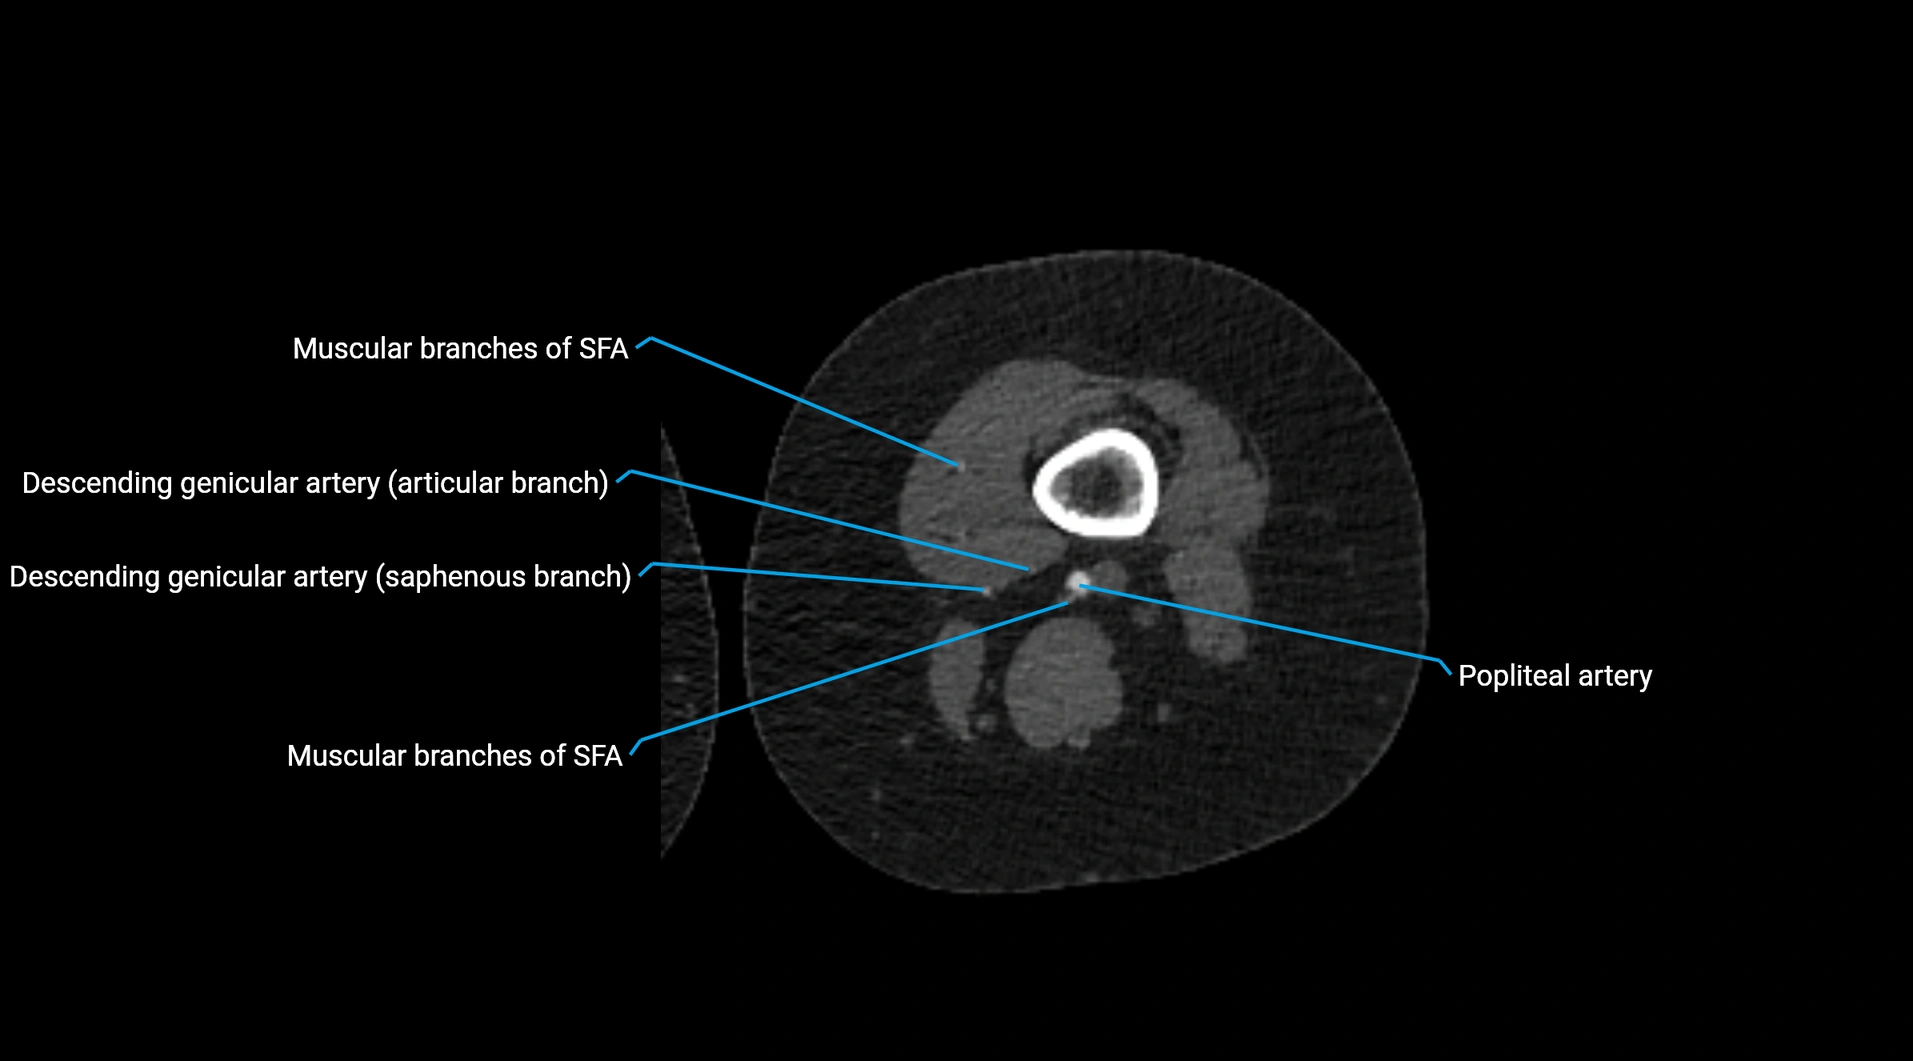

Contrast-enhanced CT (CTA):

• Gold standard for abdominal aortic imaging

• Provides excellent detail of lumen, wall, aneurysm, thrombus, and branch vessels

• Multiplanar and 3D reconstructions help in aneurysm measurement, stent graft planning, and dissection evaluation